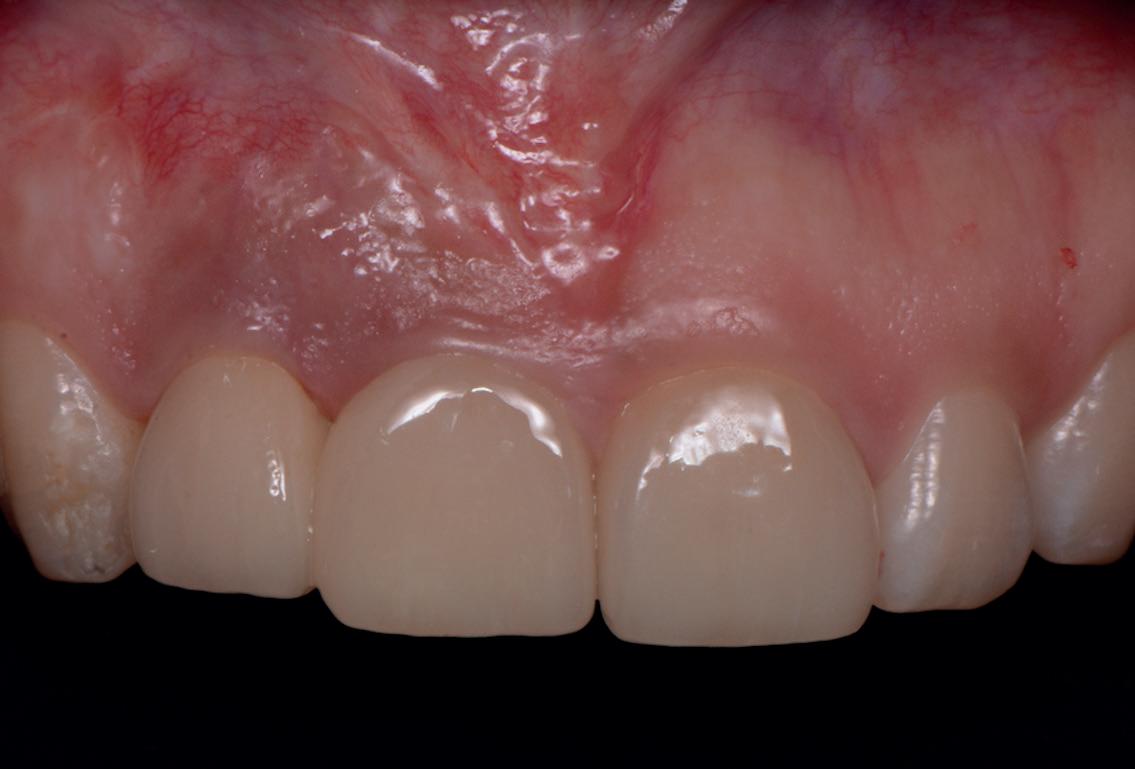

SITE AUGMENTATION Reconstituirea țesutului moale periimplantar și papilar în zona estetică

RECONSTITUIREA țesuturilor moi periimplantare. Scopul acestui raport de caz este de a demonstra procedurile chirurgicale utilizate pentru corectarea unui defect al țesuturilor moi periimplantare folosind țesutul moale interdentar în combinație cu tuberozitatea ca locație donatoare de țesut conjunctiv, utilizând o abordare prin tunelizare într-o zonă estetică.